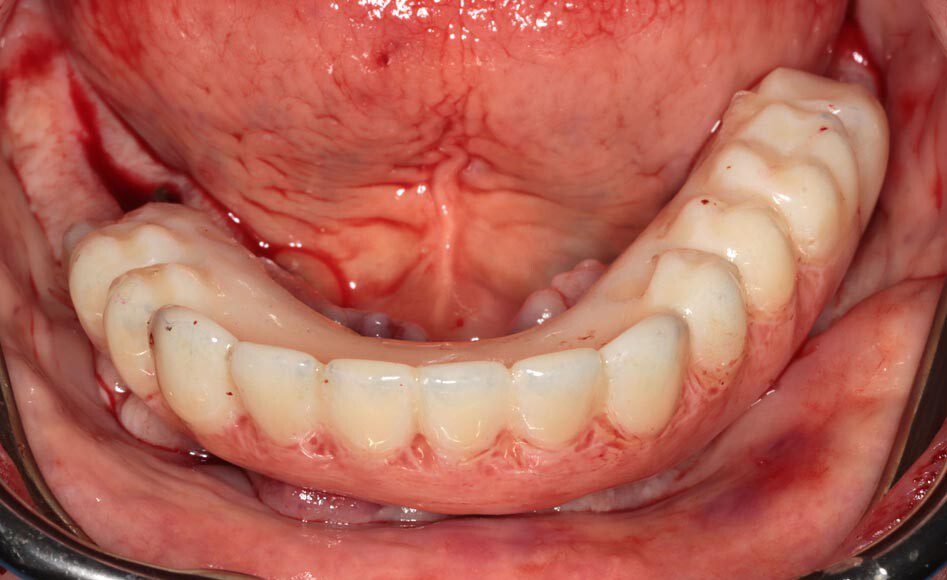

Lower teeth extracted, some bone removal lower, 8 upper implants, 5 lower implants, lower immediate temporary bridge.

Patient will continue to use his prior upper denture for three months as most of the upper implants were not stable enough for immediate temporary. After 3 months of healing, these implants will be ready for a fixed temporary bridge.